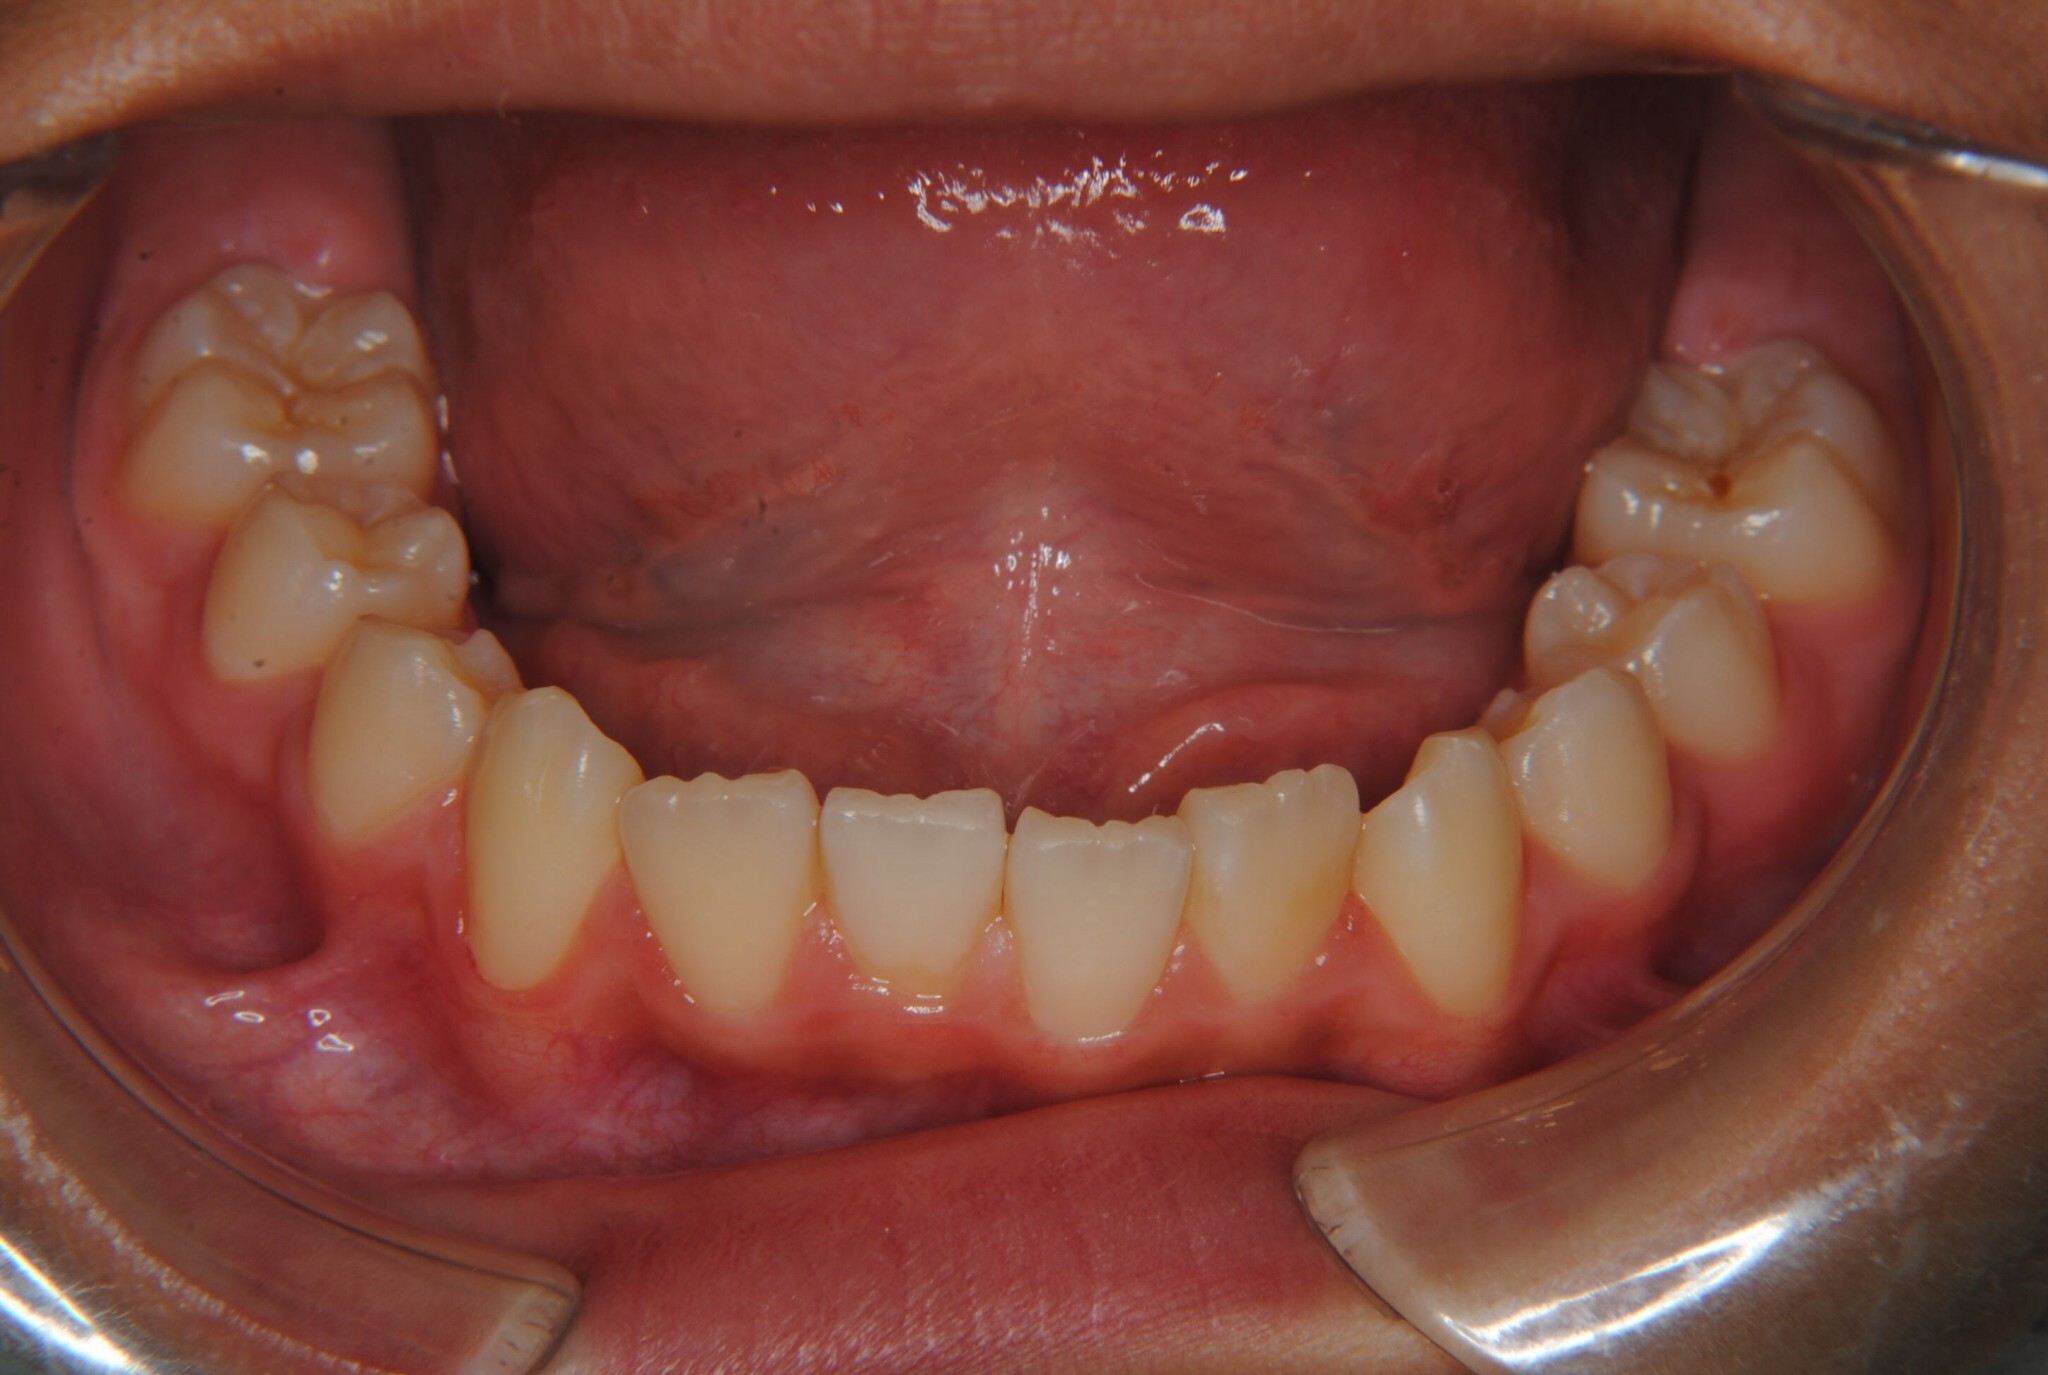

①主訴:下の前歯のデコボコ

②診断名:Ⅰ級叢生

③年齢:初診時(左写真)8歳6か月、終了時(右写真)11歳4か月

⑧リスクと副作用:特に大きなリスクや副作用はありませんでした。拡大床装着直後は違和感があったようですが、特に痛みを感じることなく6.5mmまで拡大できました。その後永久歯への生え変わりも順調で、ほぼ正常な咬み合わせになりました。この後11歳4か月まで観察し、7番目の奥歯である12歳臼歯がきちんと咬んだので終了となりました。